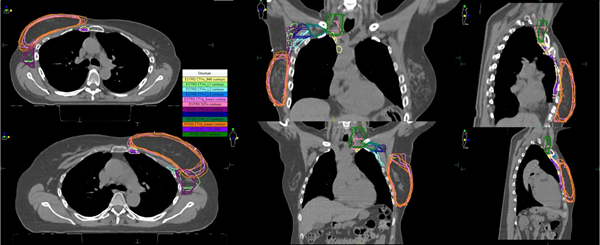

Figure 1 The target volumes produced using the ESTRO versus the RTOG guidelines in a right and left ESBC patient.

The mean volumes for each contouring target volume are presented in Table 1. There is evidence of larger target volumes contoured by the observers using the RTOG guidelines except for the CTVn_IMN contour. The estimated intra-class correlation coefficient indicates slightly higher absolute agreement for the CTVn L1, CTVn L2, and CTVn L3 target volumes according to the RTOG guidelines, although the 95% confidence intervals for these coefficients of correlation are wide. The range of mean DSC values when contouring volumes based on the ESTRO guidelines was 0.66-0.92 and the range for the RTOG guidelines was 0.62-0.90. Within each guideline, the CTVp_Breast showed the highest level of agreement between the ROs (Figure 2). CTVp_Breast was also the only volume to show a statistically significant difference in the DSC mean value (p=0.031), with 0.92 (0.04) for ESTRO guidelines compared with 0.90 (0.03) for the RTOG guidelines. The mean DSC for CTVn_IMN was 0.63 (0.10) for ESTRO and 0.62 (0.20) for RTOG guidelines thus showing the least level of agreement within both guidelines but there was no significant difference between the mean DSC values for each guidelines (p=0.84). Within the axillary nodal and SCF target volumes, there was similar agreement amongst the observers for both ESTRO & RTOG guidelines. The mean DSC values for the CTVn_L1, CTVn_L2, CTVn_L3 and SCFn ranged from 0.71-0.78 for the ESTRO guidelines and 0.70-0.80 for the RTOG guidelines. When assessing the volumes by each RO that produced the highest DSC value (CTVp_Breast), we can see clear evidence of good consistency by the close distances between the ROs volumes (Figure 3A). Whereas, the volumes that formed at the lowest DSC value (CTVn_IMN), we can see a greater degree of variation in the volumes (Figure 3B), particularly for the ESTRO guideline with one observer consistently delineating a larger volume for overall CTVn_IMN contour. This is supported by the ICCAA for the CTVn_IMN being quite low at 0.06 for the ESTRO guideline, and only slightly higher at 0.08 for the RTOG guidelines.